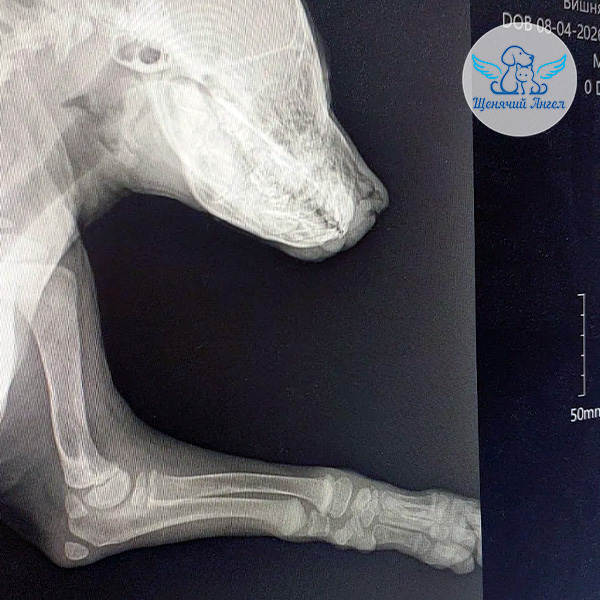

Первым делом мы показали шенулю хирургу и провели обследование 🩻. К сожалению, рентген подтвердил застарелую травму, которая привела к параличу лучевого нерва. Глубокая болевая чувствительность в лапке утрачена 😔.

Чтобы в будущем конечность не мешала Вишенке активно расти и полноценно жить, врачи рекомендуют ампутацию – такие травмы, увы, не восстанавливаются.